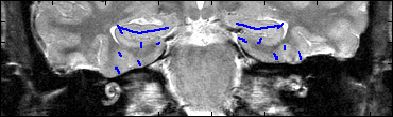

This is an example of one subjects demarcation. The A/P slice is slice

3.